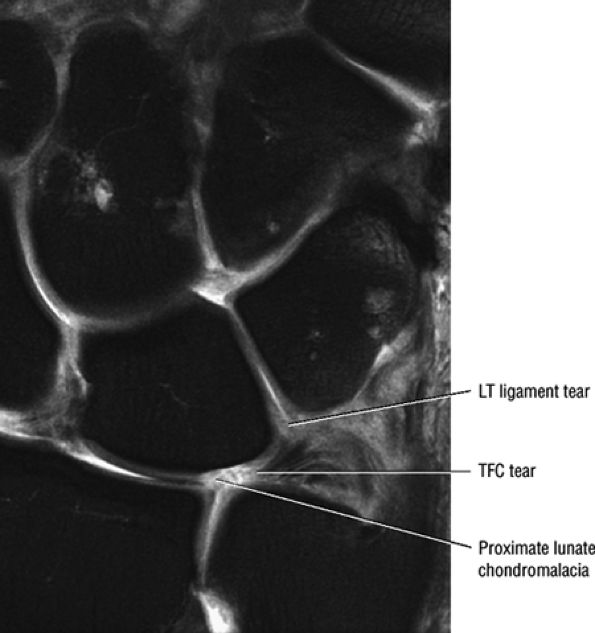

FIGURE 10.1 ● A 3D fast spoiled GRASS (FSPGR) with intra-articular contrast injected into the radiocarpal compartment. The torn lunotriquetral ligament (straight arrow) allows extension of contrast into the midcarpal compartment and the torn radial attachment of the TFC (curved arrow) directs contrast into the distal radioulnar joint. Note the superior trabecular bone detail on this image (coronal image; TR, 40.4 msec; TE, 14.5 msec; FOV, 4 cm; slice thickness, 2.0 mm; matrix, 512 × 256; flip angle, 30°).